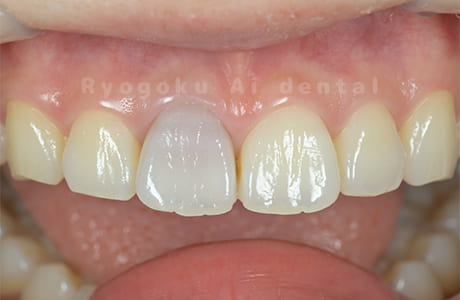

上顎前歯部の歯の神経が死んでしまったことによる1歯の変色をブリーチングにより改善したケース。